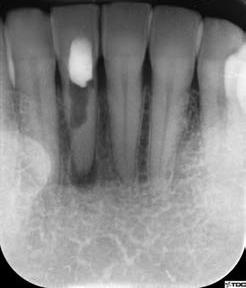

Egy 63 éves páciens korábban már kezelt bal alsó első nagyőrlőfogából (3.6) eredő mérsékelt fájdalom miatt kereste fel rendelőnket. A kórtörténetében panasza szempontjából releváns információ nem szerepelt. Az elkészült CBCT-felvételen a korábbi kezelések során észre nem vett, jelenleg feltáratlan meziobuccalis csatornát, valamint a mezialis és distalis gyökerek körül kialakult periapicalis elváltozást, és ezt a léziót borító intakt buccalis corticalis csontlemezt láttunk.

A fog revideálását és újbóli gyökértömését két ülésben végeztük el. A régi gyökértömés eltávolítását, valamint mindhárom gyökércsatorna megmunkálását és fertőtlenítését követően kalcium-hidroxid alapú gyógyszeres zárást helyeztünk a gyökércsatornákba. A gyökértömés egy héttel később került behelyezésre. A páciens panaszai két hónap elteltével sem szűntek.

Klinikai vizsgálat során vertikális kopogtatási érzékenységet jelzett. A fog körül mérhető szondázási mélység és a fogmobilitás fiziológiás volt. A CBCT-felvételen nem észleltünk a csontos regeneráció megindulására utaló jeleket (1. a–c. ábrák). A korábban gyökérkezelt, gyökértömött és revideált 3.6-os fog esetében az alábbi diagnózis került felállításra: periodontitis periapicalis symptomatica. A panaszokat okozó fog további ellátása során navigált endodonciai mikrosebészetet kívántunk alkalmazni. Az alsó állcsontról intraorális szkent (TRIOS, 3Shape) készítettünk, és a felszíni topográfiát tartalmazó STL fájlt, valamint a CBCT-felvétel készítése során nyert DICOM fájlokat a Blue Sky Bio szoftver segítségével egyesítettük. A sebészi sablon megtervezésére az így kapott háromdimenziós képet használtuk. A sablon kialakítása során arra törekedtünk, hogy a sablon egyértelműen meghatározza a gyökércsúcsi terület eléréséhez szükséges csontablak határait (1. d. ábra)